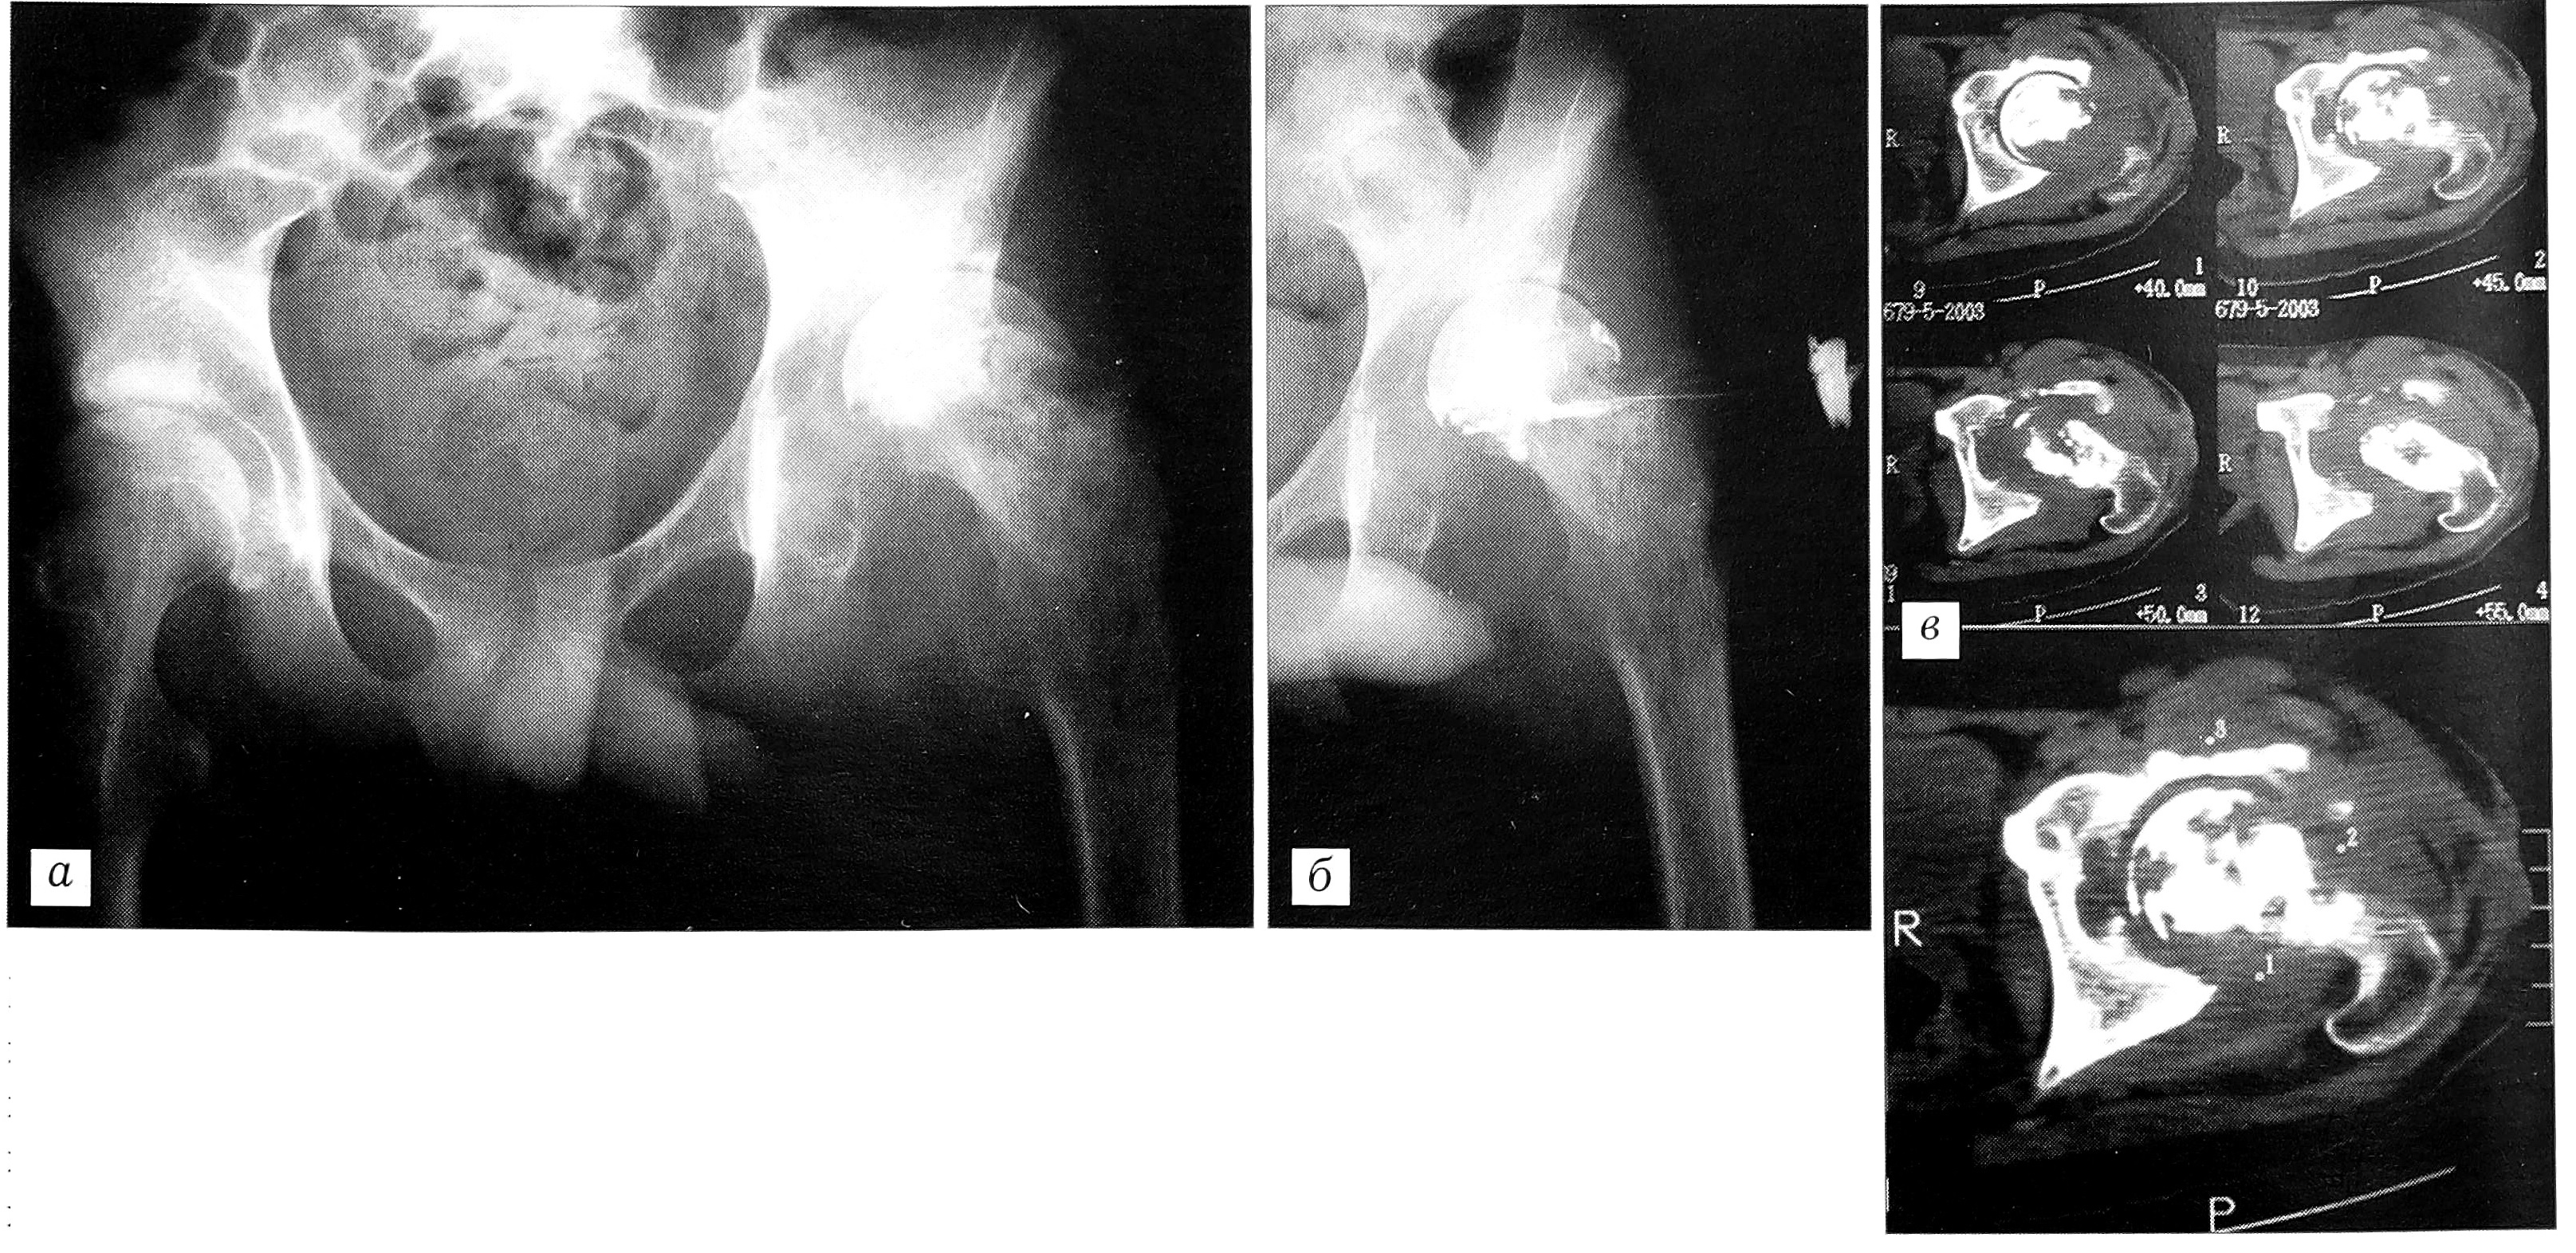

У пациентов с остеомиелитическим поражением проксимального конца бедренной кости и вертлужной впадины без металлоконструкций, кроме рентгенографии, выполняли компьютерную томографию для уточнения объема и распространенности поражения, степени разрушения тазобедренного сустава, что особенно важно при бессвищевых формах острого и хронического гематогенного и посттравматического остеомиелита (рис. 4).

Рис. 4. Рентгенограмма (а), фистулограмма (б) и компьютерная томограмма (в) больного С. 15 лет при поступлении. За 1 год до поступления была вскрыта нагноившаяся гематома на левом предплечье. Послеоперационный период осложнился развитием сепсиса. Через 2 мес диагностирован остеомиелит головки левой бедренной кости, выполнена артротомия, сформировался свищ.